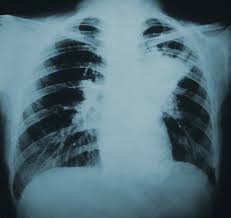

폐암은 폐에 있는 세포가 비정상적으로 증식하는 질환으로, 크게 비소세포폐암과 소세포폐암으로 나뉩니다. 대부분은 비소세포폐암에 해당하며, 소세포폐암은 진행이 빠르고 전이가 잘 되는 특징이 있습니다.

폐는 산소와 이산화탄소를 교환하는 중요한 기관이므로, 암이 발생하면 호흡 기능에 치명적인 영향을 줍니다.

특히 흡연력 있는 40세 이상 성인은 저선량 CT 검진을 권장합니다.